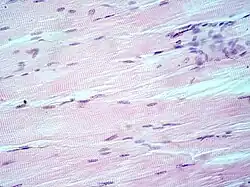

Micrografía de un corte transversal de músculo esquelético estriado. En la periferia de cada célula sincitial se observan varios núcleos.

Corte longitudinal de músculo esquelético.

El músculo esquelético es considerado un verdadero sincitio anatómico, pues cada célula presenta múltiples núcleos, originada por la fusión de múltiples células. Los mioblastos comienzan a multiplicarse, influidos por factores de crecimiento como el FGF. Los receptores integrinas de las fibronectinas y otras moléculas como las cadherinas los obligan a reconocerse, alinearse y adherirse, para posteriormente fusionarse en células musculares sincitiales. Este último proceso está mediado por meltrinas —unas metaloproteasas—.[12]​ En cultivo, los mioblastos forman el sincitio al proliferar y fusionarse mientras producen proteínas contráctiles. Este proceso es cooperativo, de tal forma que la fusión celular altera el medio de cultivo para inducir la fusión de otros mioblastos.[29]

El sincitio del músculo esquelético permite una rápida contracción coordinada de los músculos en toda su longitud. El potencial de acción se propaga a lo largo de la superficie de la fibra muscular desde el punto de contacto sináptico con la neurona motora.[30]​ En estados patológicos como la miopatía, la presencia de sincitio permite la viabilidad muscular, porque los focos de necrosis de una parte del músculo esquelético no resultan en la necrosis de las secciones adyacentes de esa zona ya que estas regiones tienen su propio material nuclear, aunque algunos de los segmentos supervivientes queden sin inervación por la pérdida de continuidad con la unión neuromuscular.[31]